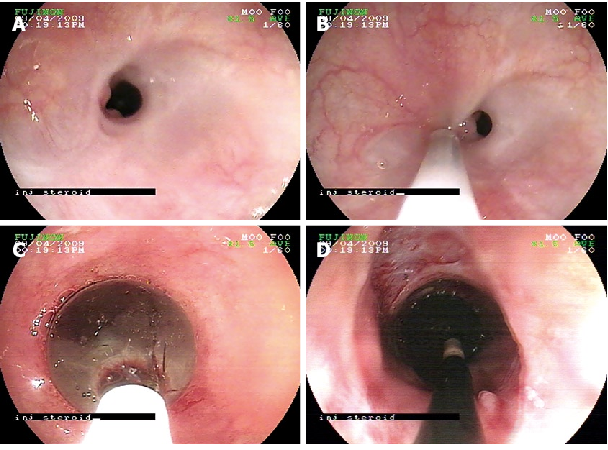

Ösophagus-Strikturen

👉 Verengungen des Lumens.

- Ursachen:

- Narbig nach chronischem Reflux (peptische Striktur)

- Verätzungen (Säure/Laugen)

- Nach Radiotherapie oder OP

- Klinik: Dysphagie, Bolus steckt fest

- Diagnostik: Endoskopie mit Biopsie (Tumor ausschließen)

- Therapie: Endoskopische Dilatation, ggf. Stent